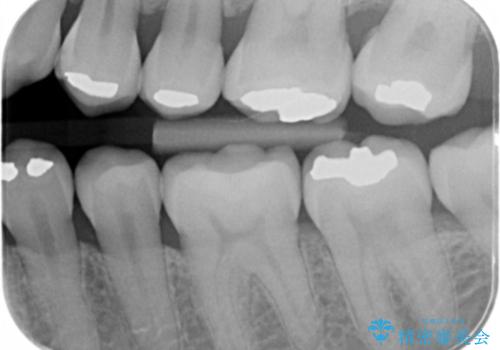

- 劣化したプラスチックとアマルガムをはずしてセラミックにしていく治療を行いました。

アマルガムは水銀が含まれている為、外したい方が増えています。

- 左下6番、左下7番 セラミックインレー 7.7万円×2本費用は治療当時の料金となります

①初回 アマルガム、古い詰め物の除去、虫歯の除去

裏打ちをしく、インレーの形として整える、シリコンを使用した歯型とり